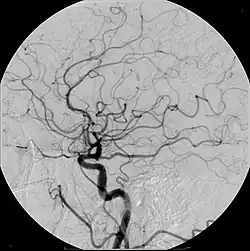

- Angiography (arterial investigations)

Iodinated contrast contains iodine. It is the main type of radiocontrast used for intravenous administration. Iodine has a particular advantage as a contrast agent for radiography because its innermost electron ("k-shell") binding energy is 33.2 keV, similar to the average energy of x-rays used in diagnostic radiography. When the incident x-ray energy is closer to the k-edge of the atom it encounters, photoelectric absorption is more likely to occur. Its uses include: